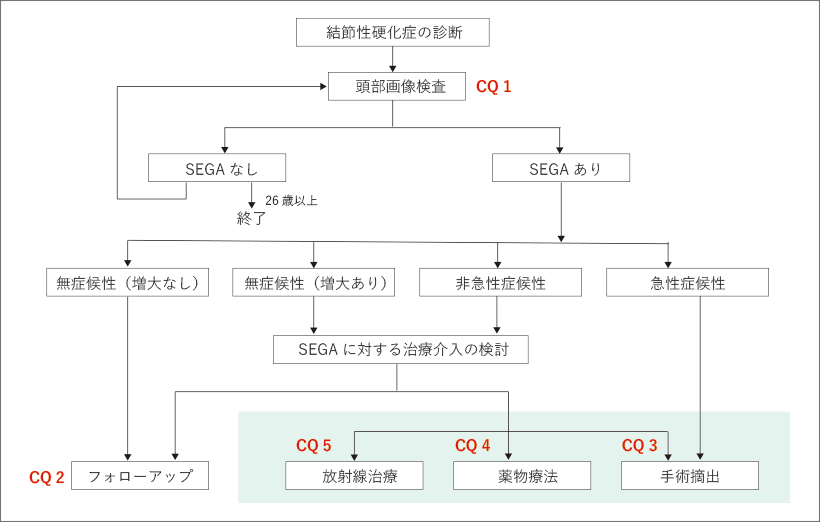

沖縄県医師会_沖縄県医師会報(2012年4月号), 日本脳腫瘍学会オフィシャルホームページ! Welcome to Japan,

日本脳腫瘍学会オフィシャルホームページ! Welcome to Japan, 朝倉書店『内科学』(第12版)デジタル付録,

朝倉書店『内科学』(第12版)デジタル付録, 頭蓋骨腫瘍 skull tumor | 脳外科医 澤村豊のホームページ,